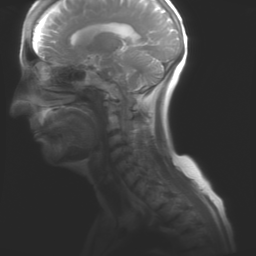

I’m so grateful for my home, my garden, my family, and my friends. With every breath, I thank God. I’m so very thankful we passed another cancer milestone. The tumors in my brain have responded so favorably to the Gamma Knife surgery that Dr. Pollack said my images would be the ones he would show at a conference.

The five tumors are nearly non-existent.

My scans are an example of surgery success to the nth degree. Sure, the nerve damage to my left ear will always be there; but I told the doctor I would take it in exchange for “no new lesions” in my brain. My friend Nancy said the ringing from tinnitus is a reminder of God’s tender mercies, a healing. And, if I make it to January with clean scans, we move to an “every six-month” schedule for the tests. Today, I have been given another three-month lease on life.